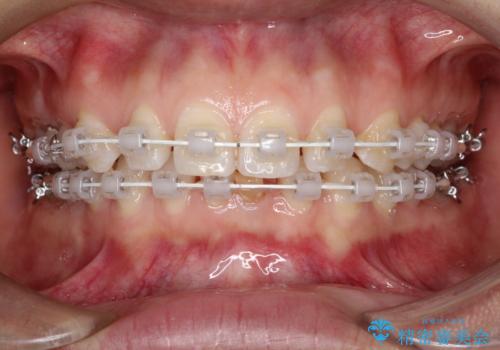

- 矯正装置

- 審美装置

- 治療期間

- 1年

短期間での治療終了を希望され、ワイヤー矯正にて治療を行い1年ほどで治療を終了しております。